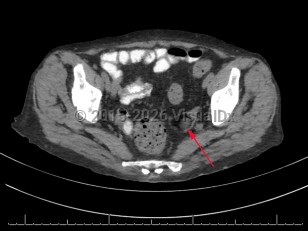

Imaging Studies image of Teratoma of ovary - imageId=7878204. Click to open in gallery.  caption: '<span>Axial CT demonstrating a fat-containing left adnexal lesion (arrow), consistent with a mature cystic teratoma.</span>'

Axial CT demonstrating a fat-containing left adnexal lesion (arrow), consistent with a mature cystic teratoma.